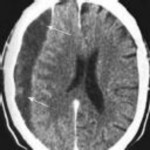

Figures 1 and 2 show a sagittal CT scan and a clinical photograph from a 16-

year-old boy who was found unresponsive after a diving accident. He had to be extricated from the bottom of a swimming pool by friends and was intubated at the scene by paramedics. In the emergency department, he was found to have weak triceps and grip strength bilaterally. Lower extremity strength was trace (grade 1 of 5). Sensation was diminished below the T2 dermatome. He had an absent bulbocavernosus reflex. Immediate open posterior reduction and stabilization were performed. Postoperative MRI revealed no iatrogenic disk herniation. Postoperative neurologic function revealed grade 4 strength in the triceps, wrist flexors, and bilateral grip. His lower extremity strength was grade 3. The sensory examination showed only slight diminution in the legs bilaterally. His bulbocavernosus reflex returned on postoperative day 2. On postoperative day 3, he required reintubation and was noted to require high positive end-expiratory pressures and a high ventilatory rate to keep him oxygenated. On postoperative day 4, his temperature was 38.7° C, blood pressure was 90/48, and pulse was 110 beats per minute. The urinary output measured 32 ml per hour. The white blood cell count was 14.8 with a left shift. A chest CT was ordered, and the results are shown in Figure 3. What best describes his condition?

4. Septic shock Discussion: D

Aspiration pneumonia developed, as seen on CT, and presumably occurred during his near drowning accident. His laboratory values and hemodynamic status are characteristic for septic shock. His original neurologic injury is an incomplete spinal cord injury, but after reduction and stabilization, he showed neurologic improvement, so this injury should not have contributed to his circulatory problems. The treatment for septic shock is broad spectrum antibiotics (species specific if the pathogen is identified) and pressors.